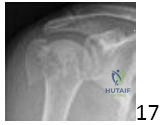

An 82-year-old female with severe osteopenia falls from a standing height, sustaining a 4-part valgus-impacted proximal humerus fracture, as shown in the image below. She has limited pre-injury shoulder function due to long-standing rotator cuff arthropathy and a low demand lifestyle.